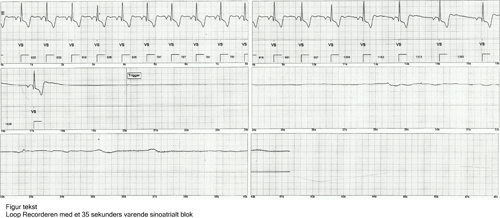

En kvinde i starten af tresserne havde gennem tredive år haft tendens til synkope, der forekom i både hvile og ved fysisk aktivitet. Anfaldende kom cirka en gang om året, uden prodromer. Der var ingen ekskretafgang eller tungebid, patienten vågnede hurtigt op efter synkoperne og var klar og relevant. Hun var udredt i neurologisk og kardiologisk regi. Blodtrykket, biokemiske prøver, elektroencephalografi, CT af cerebrum, ekkokardiografi, Holter monitorering samt ekstern event recorder havde vist normale resultater. Man kunne ikke udelukke længerevarende asystoli eller arytmi, hvorfor man tilbød implantation af en loop recorder. Nogle måneder efter kom patienten ind efter et anfald. Loop recorderen blev udlæst og viste et 35 sekunders varende sinoatrialt blok (fig 1), hvorefter patienten straks fik en pacemaker. Siden har hun været asymptomatisk.